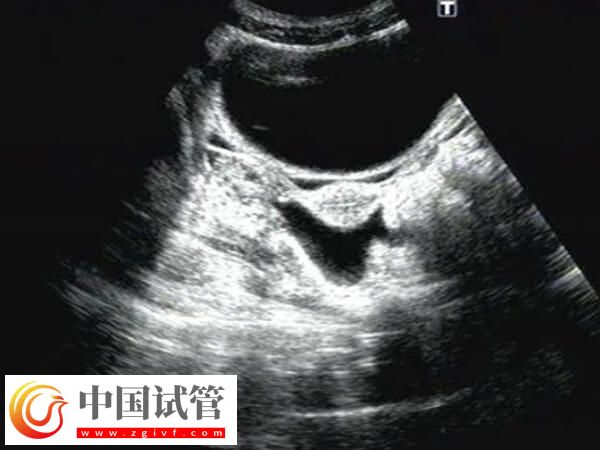

試管囊胚移植40天宮腔有積液的干凈時間不可一概而論,還需要根據(jù)實(shí)際情況進(jìn)行判斷,畢竟每個患者身體情況不同多樣積液消失時間也會有差異,建議出現(xiàn)宮腔積液的患者,應(yīng)該定期進(jìn)行超聲檢查,監(jiān)測積液的變化,然后根據(jù)醫(yī)生的建議進(jìn)行適當(dāng)?shù)谋Lゴ胧?/h5>囊胚移植后子宮積液怎樣能排出

囊胚移植后40天有子宮積液會增加流產(chǎn)風(fēng)險,但大部分超聲提示的少量積液在沒有明顯陰道出血的情況下,并不一定意味著會發(fā)生流產(chǎn),所以患者無需過度緊張,至于患者在囊胚移植后40天發(fā)現(xiàn)子宮積液,要怎樣才能排出,對此感興趣的可參考下列內(nèi)容: